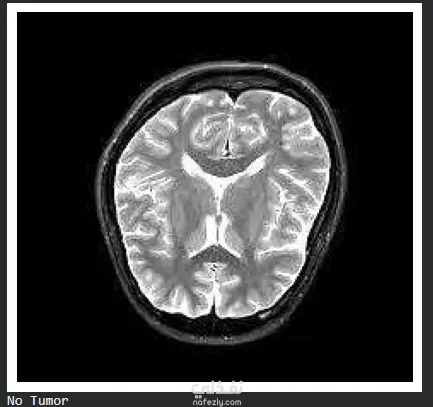

مشروع متكامل في مجال الذكاء الاصطناعي (Machine Learning) يهدف إلى دعم التشخيص الطبي من خلال تحليل صور الرنين المغناطيسي (MRI) لاكتشاف وتصنيف أورام الدماغ بدقة عالية. أبرز ما تم تنفيذه في المشروع: معالجة البيانات (Data Preprocessing): تنظيف وتحسين الصور الطبية لزيادة الوضوح وتقليل الضوضاء لضمان دقة النتائج. بناء النموذج (Modeling): استخدام تقنيات التعلم العميق (Deep Learning) وخوارزميات الـ CNN لبناء نموذج قادر على التمييز بين أنواع الأورام المختلفة. التقييم (Evaluation): اختبار النموذج والتأكد من تحقيقه لمعدلات دقة (Accuracy) و Precision عالية لتجنب الأخطاء في التشخيص. Optimization: تحسين أداء الموديل ليكون خفيفاً وسريعاً في استخراج النتائج.